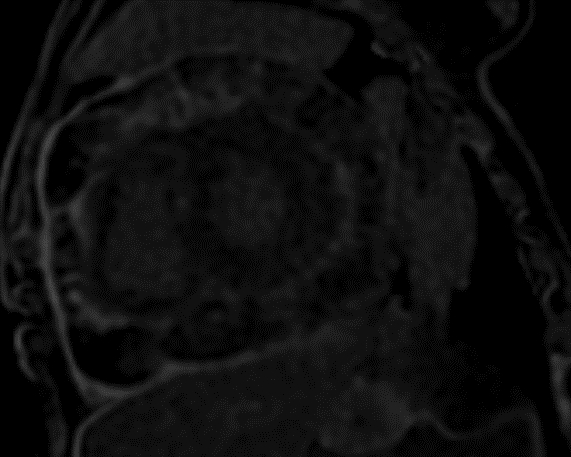

A 33-year-old man with no medical history or environment exposures, presented with dyspnea, nausea, and vomiting. He was tachycardic, with jugular venous distension, pulsus paradoxus, low voltage QRS and echocardiogram (TTE) showed a large pericardial effusion with ventricular interdependence. He underwent pericardiocentesis with negative fluid studies, including cytology. Two months later he represented with dyspnea and pleuritic chest pain, was diagnosed with pericarditis, and found to have recurrent pericardial effusion without tamponade. He was treated with aspirin and colchicine and discharged, with surveillance TTE showing a stable pericardial effusion but with significant adhesions and constrictive physiology (confirmed on right heart catheterization). Negative QuantiFERON was obtained and Anakinra started. Two months later he remained symptomatic with new pleural effusions and was sent for positron emission tomography scan which revealed diffuse intensely hypermetabolic pericardial thickening/fluid, up to 3.8 cm in maximal thickness and increased uptake in mediastinal nodes. Next, a cardiac MRI showed extensive circumferential thickening of the pericardial space approximately 2.5 cm in thickness. Both the visceral and parietal pericardium exhibited extensive scattered delayed hyperenhancement. Subsequent pericardial biopsy showed markedly fibrotic pericardium and pathology showed biphasic malignant pericardial mesothelioma. Immunosuppressive medications were stopped, and he underwent thoracentesis. After multidisciplinary discussions, he was started on nivolumab every two weeks and ipilimumab with a plan for surgery based on response to therapy. However, progressive symptoms and worsening constriction physiology led to palliative consultation and comfort care transition, with him dying shortly after.